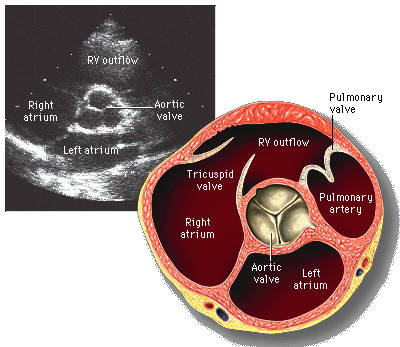

• Cardiac Echocardiography: Basics and Uses

• Anatomy and Physiology of the Heart